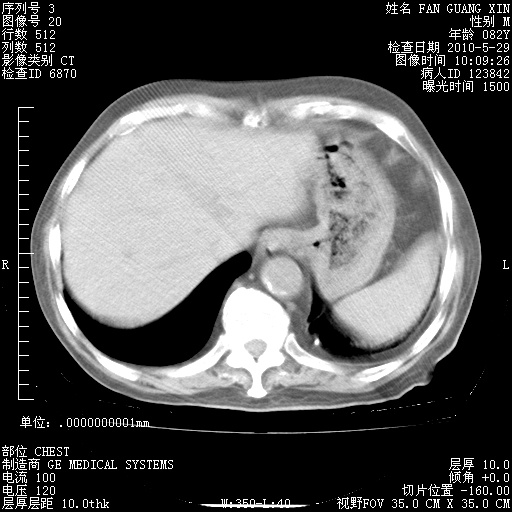

再治疗10天后的肺部CT 纵膈窗

从白细胞总数和中性比例看好像合并感染。肺部纹理好像比上次多,支气管炎?其他感染?

阅读此次胸部CT,肺间质渗出性改变较入院时有吸收。目前从体温、白细胞、中性分叶明显增高,肯定存在细菌感染(发生医院感染哦,若无消化道及泌尿系统等感染的依据,肺部感染可能大)。若你院头孢哌酮舒巴坦钠耐药率较高,同意你的方案,若48小时体温仍高,可考虑使用碳青霉稀类抗菌药物,同时可予超声雾化、注意滴数时加大液体量。白蛋白33.30g/L较低哦,需加强营养等支持治疗。